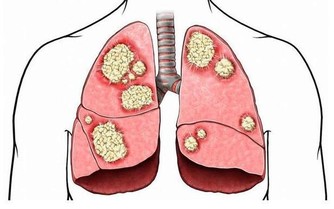

7、經常咳嗽,或支氣管、肺部等發炎;